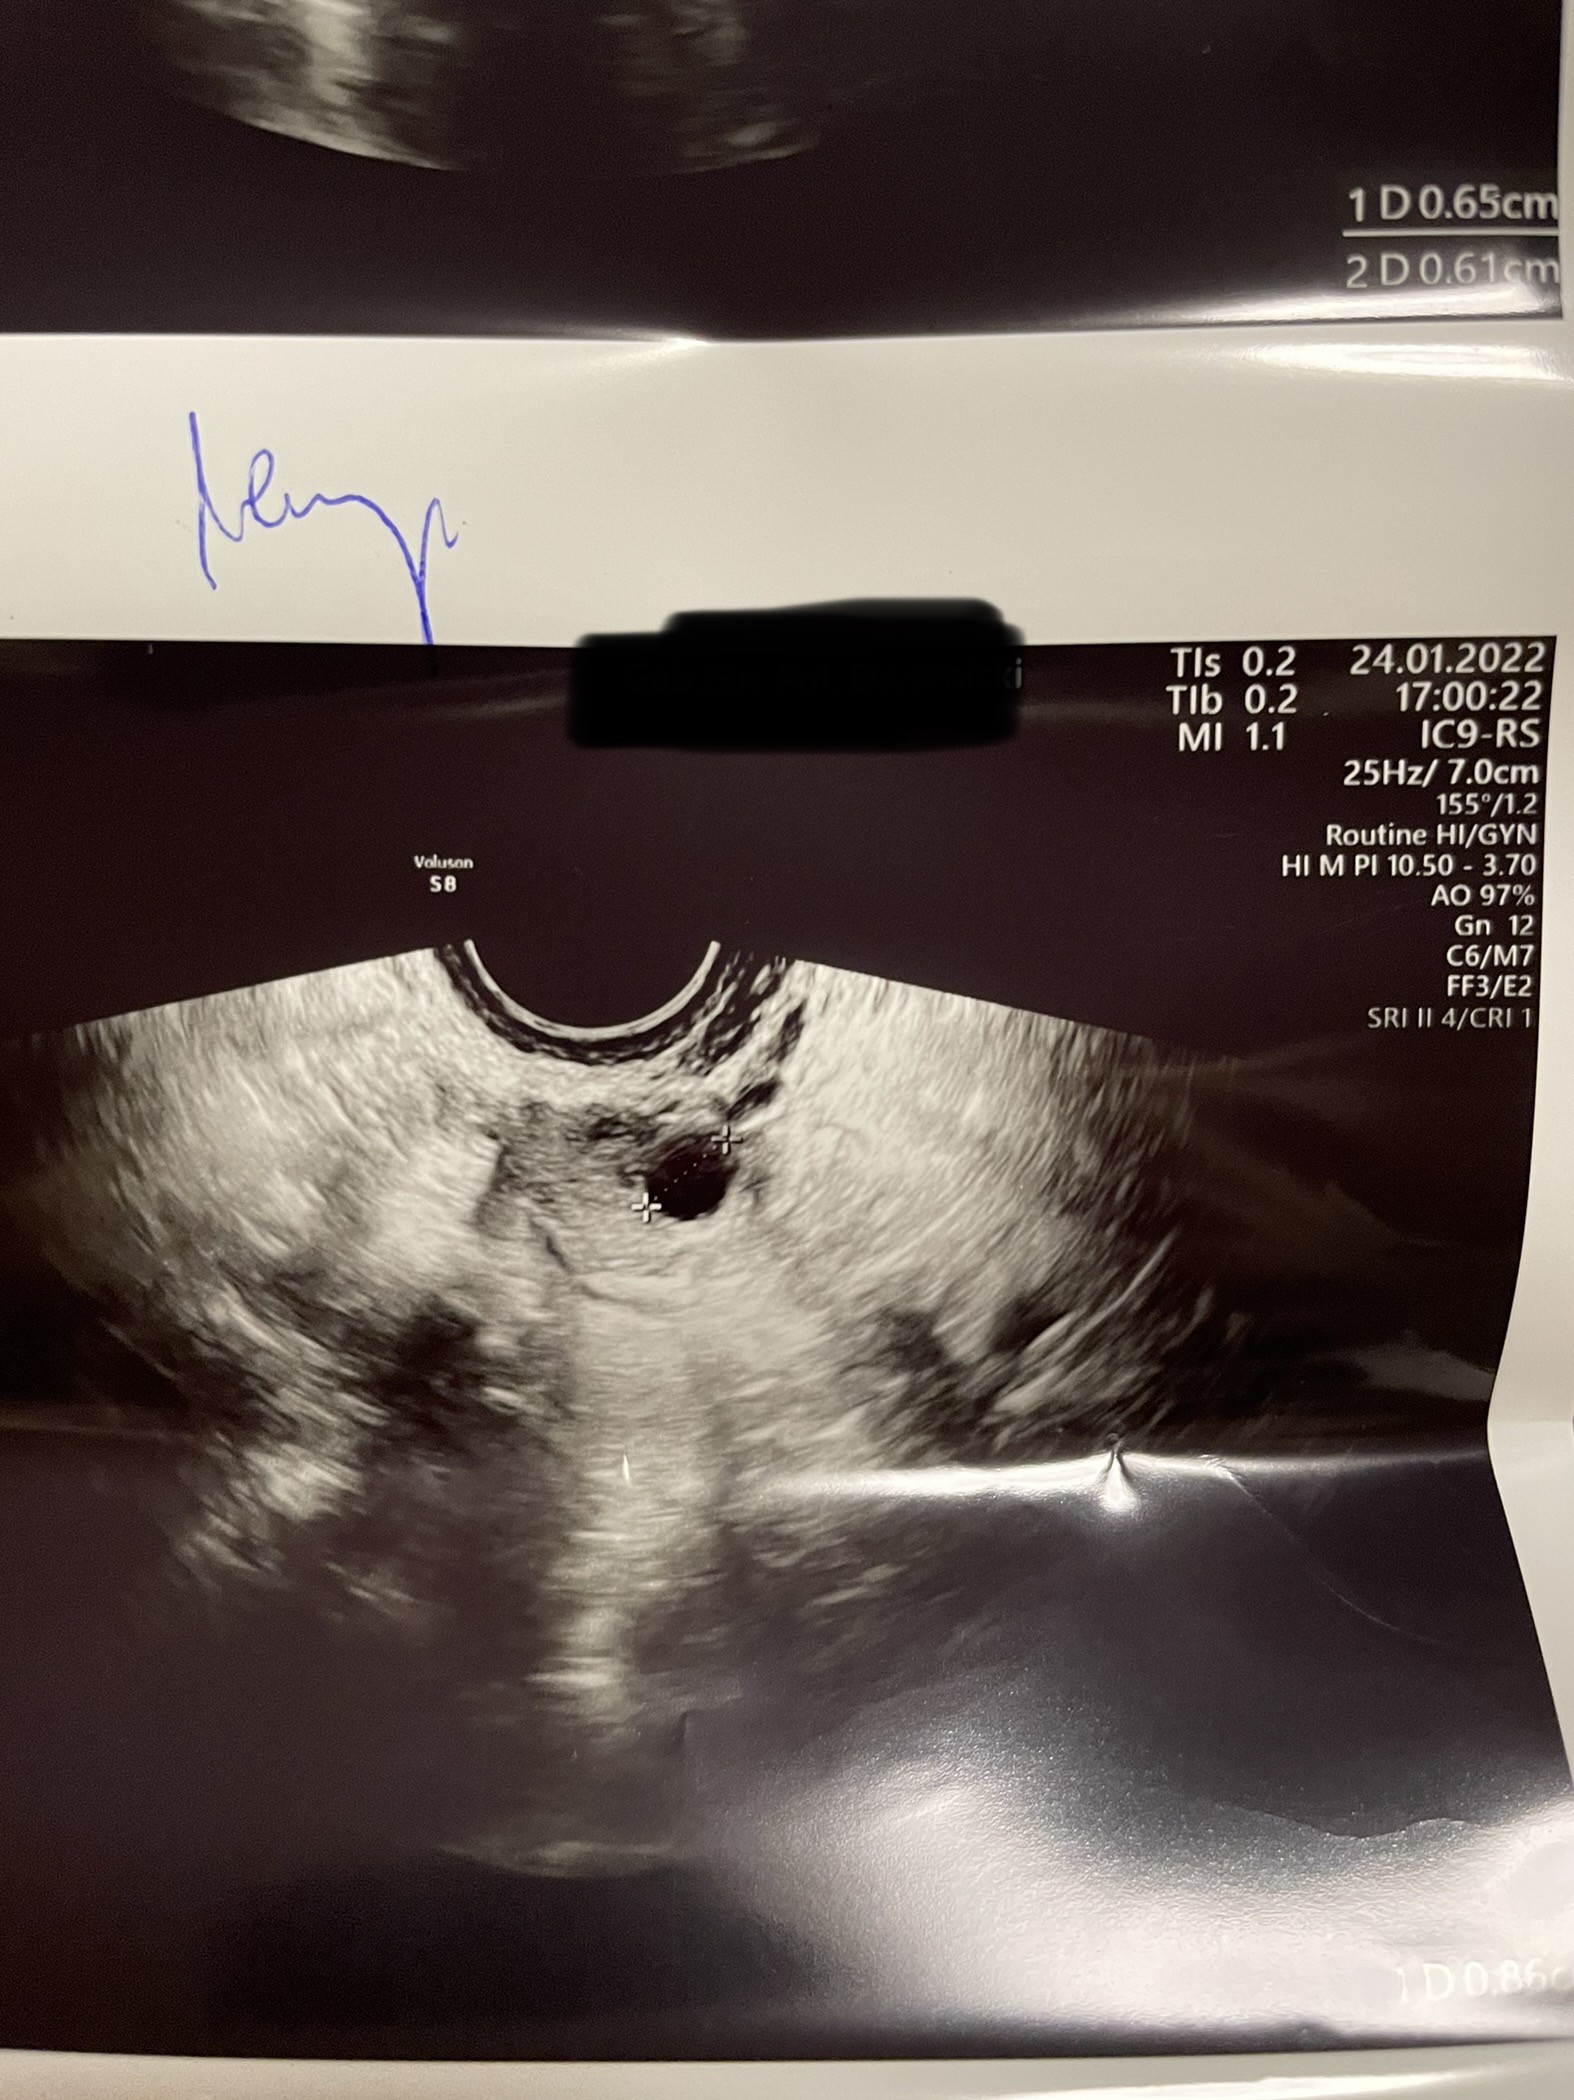

Hej, już po wizycie a wiec

Jajnik lewy

Pęcherzyk pierwszy 0.61cm

Pęcherzyk drugi 0.65cm

Jajnik prawy pęcherzyk 0.86cm

Endomedrium 0.72cm

Dziś 7DC następna wizyta w czwartek

Czekaj… ta są wszystkie pecherzyki poniżej 10mm, więc ich w ogóle powinno być więcej (nawet kilkanaście) w każdym jajniku, to nie są pecherzyki dominujące. Chyba, ze 1,61, 1,65 i1,86?

Pęcherzyk dominujący mam w prawym jajniku. W lewym mam 2 tylko (aż). Dopiero rosną, w czwartek zobaczymy jak duże będą.